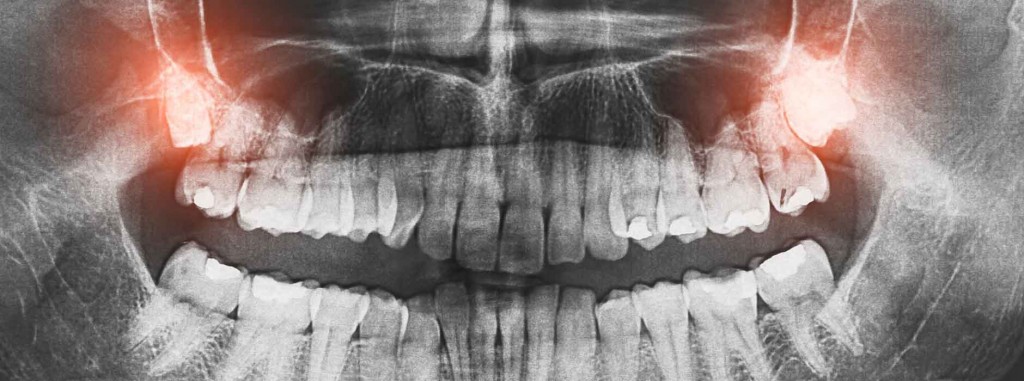

Wichtige informationen zur weisheitszahn op. Bricht der weisheitszahn nicht durch den kiefer, kann er entzündungen hervorrufen und zu einem krankheitsherd werden. Drei möglichkeiten, die weisheitszähne zu ziehen. Die meisten menschen sind 18 bis 25 jahre alt, manchmal sogar noch älter, wenn der weisheitszahn kommt. Bei 80 prozent aller jungen erwachsenen reicht der platz im kiefer für die weisheitszähne nicht aus. Wann ein weisheitszahn gezogen werden sollte und wie die operation abläuft, lesen sie hier. Wann kann man wieder essen nach der op? Weisheitszähne haben ihre berechtigung in der evolutionsgeschichte der menschheit. Alle anderen sind schon da, und dann kommen sie zum vorschein: Normalerweise hat ein mensch vier weisheitszähne, in jedem gebissquadranten einen. Ob und wann ein weisheitszahn gezogen werden muss, erfahren sie im nachfolgendem inhalt. Was bei zahnschmerzen hilft und wann die weisheitszähne gezogen werden müssen. Wann ist eine entfernung der weißheitszähne notwendig und wie funktioniert sie?

Das internet ist eine fundgrube an informationen. Der weisheitszahn (synonyma dritter molar, lateinisch dens sapiens, dens serotinus ‚spät kommend') ist von der mitte aus gezählt der achte zahn im menschlichen gebiss. Bei 80 prozent aller jungen erwachsenen reicht der platz im kiefer für die weisheitszähne nicht aus. Wann muss man die weisheitszähne ziehen? Die jameda zahnärzte informieren sie!